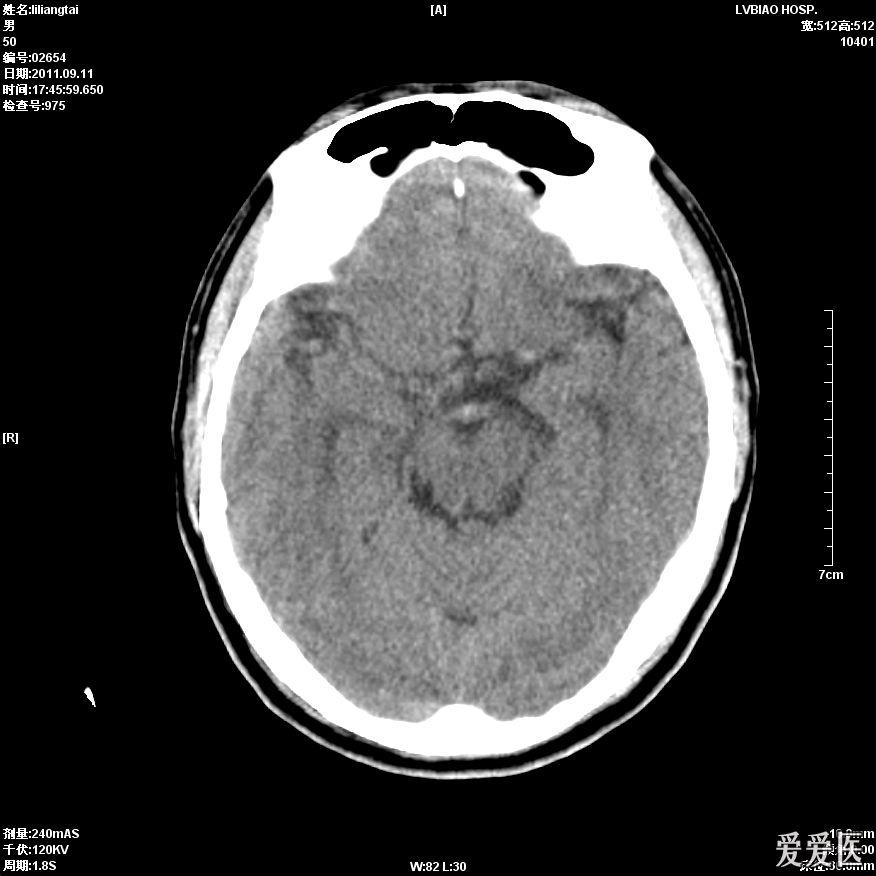

急诊ct提示左侧大脑中动脉高密度影.

左侧大脑中动脉高密度征